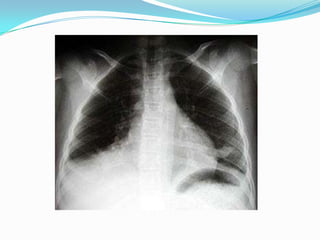

EXAMENESBroncoscopia Radiografía de tórax: Detecta los siguientes signos radiológicos:Desplazamiento de las cisuras.Desplazamiento de mediastinoElevación del hemidiafragma.Aproximación arcos costales.Enfisema compensador.Aumento de la densidad pulmonar sin broncograma.En el adulto previamente sano que presente una atelectasia hay que sospechar una neoplasias que obstruye el bronquio.

EXAMENESBroncoscopia Radiografía detórax: Detecta los siguientes signos radiológicos:Desplazamiento de las cisuras.Desplazamiento de mediastinoElevación del hemidiafragma.Aproximación arcos costales.Enfisema compensador.Aumento de la densidad pulmonar sin broncograma.En el adulto previamente sano que presente una atelectasia hay que sospechar una neoplasias que obstruye el bronquio.